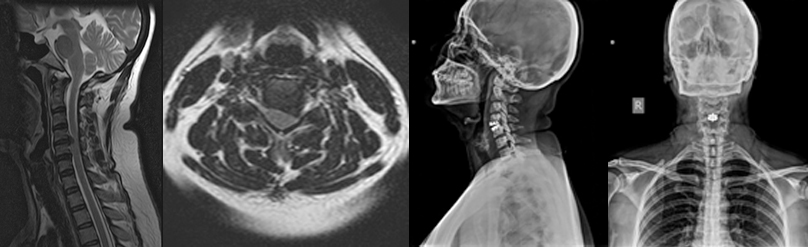

There are numerous disorders present at birth that affect the Craniovertebral Junction. These disorders may occur in isolation or be part of a generalised anomaly like Achondroplasia, Down Syndrome, Mucopolysaccharoidosis, Osteogenesis-Imperfecta, etc. Craniovertebral junction disorders may also occur later in life. They can result from motor vehicle accident, fall from a height, and certain disorders like Rheumatoid arthritis, Paget’sDisease, Ankylosing spondylitis etc. Various imaging methods like MRI, CT Scan, X rays are used for diagnosis.